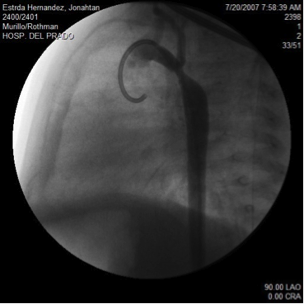

El laboratorio de cateterismos tiene grandes cámaras para ayudarle al doctor a tomar estas imágenes, y múltiples monitores de TV para ver las imágenes. Pudiera asustarle un poco a su niño, pero ese no es el propósito. Se ve algo así como la foto que sigue: